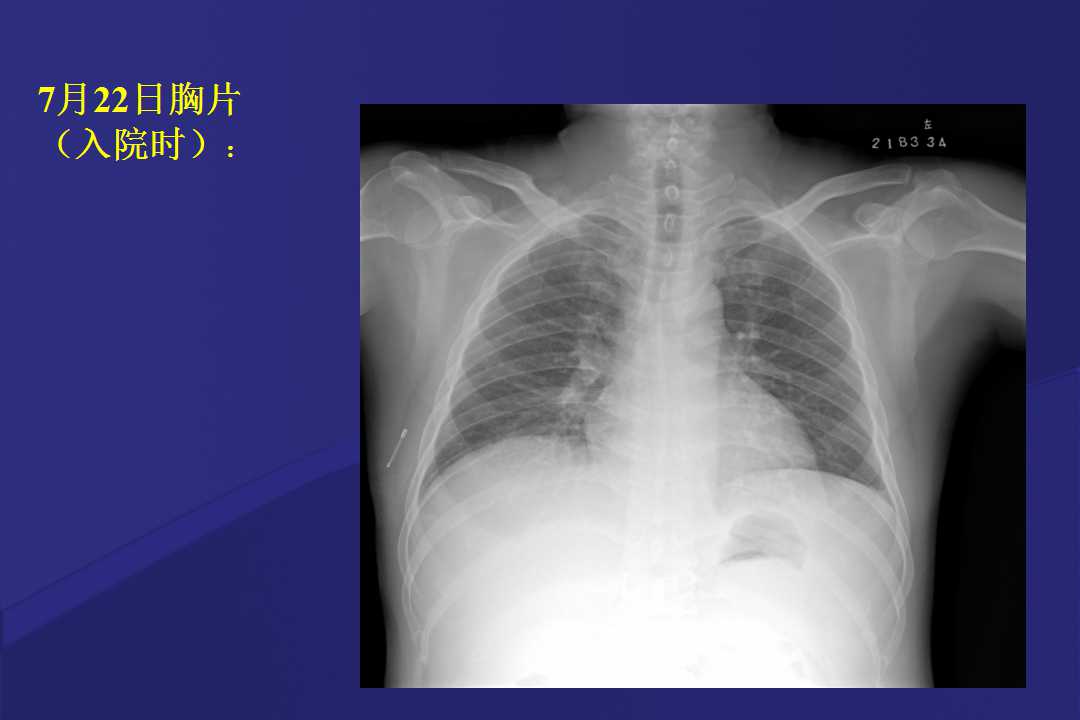

血液疾病患者肺部并发症影像学表现